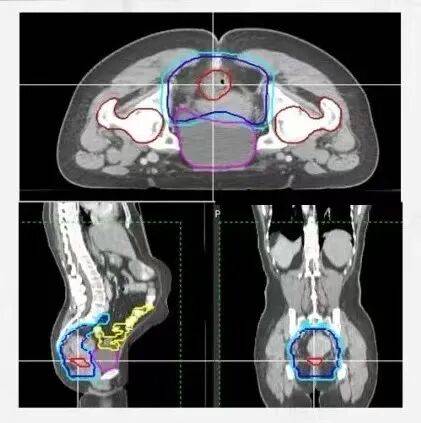

2. 新辅助放化疗——为保肛创造条件的“先遣部队”

对于局部进展期的直肠癌,我们常规开展新辅助放化疗。即在手术前,先通过放疗和化疗使肿瘤缩小、降期。这常常能将原本“不可切除”或“无法保肛”的肿瘤,转变为“可切除”且“有望保肛”的状态,大大提高了保肛手术的成功率。